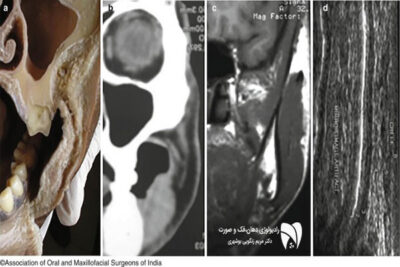

یکی از مهمترین تحولات در تصویربرداری دندان، معرفی سیستمهای تصویربرداری سهبعدی مانند CBCT است. این فناوری با ارائه تصاویر دقیقتر و واضحتر، امکان بررسی دقیق ساختارهای دهان و فک را فراهم میکند. CBCT بهویژه در تشخیص مشکلات پیچیده مانند تومورها، تحلیل استخوان، و جراحیهای ایمپلنت بسیار موثر بوده است. سیستمهای CBCT با استفاده از تکنولوژی دیجیتال، به دندانپزشکان این امکان را میدهند تا تصاویر سهبعدی از فک و دندان بیماران تهیه کنند. این تصاویر به تشخیص بهتر مشکلات و ارائه برنامههای درمانی دقیقتر کمک میکنند. به همین دلیل، CBCT به یکی از ابزارهای اصلی در کلینیکهای رادیولوژی فک و صورت تبدیل شده است.

ظهور تصویربرداری سهبعدی تحولی بنیادین در این حوزه ایجاد کرده است. این تکنولوژی، دقت و کارایی در تشخیص مشکلات دندان و فک را به حدی رسانده که روشهای سنتی دیگر قابل رقابت با آن نیستند.

تصویربرداری سهبعدی (CBCT) از تکنولوژی پیشرفتهتری نسبت به رادیوگرافی معمولی استفاده میکند. در حالی که رادیوگرافی معمولی فقط تصاویر دوبعدی ارائه میدهد، CBCT تصاویر سهبعدی از ساختارهای دندان و فک تهیه میکند. این تصاویر دقت بالاتری دارند و برای تشخیص مشکلات پیچیدهتر مانند تحلیل استخوان یا برنامهریزی جراحی ایمپلنت بسیار مناسب هستند.